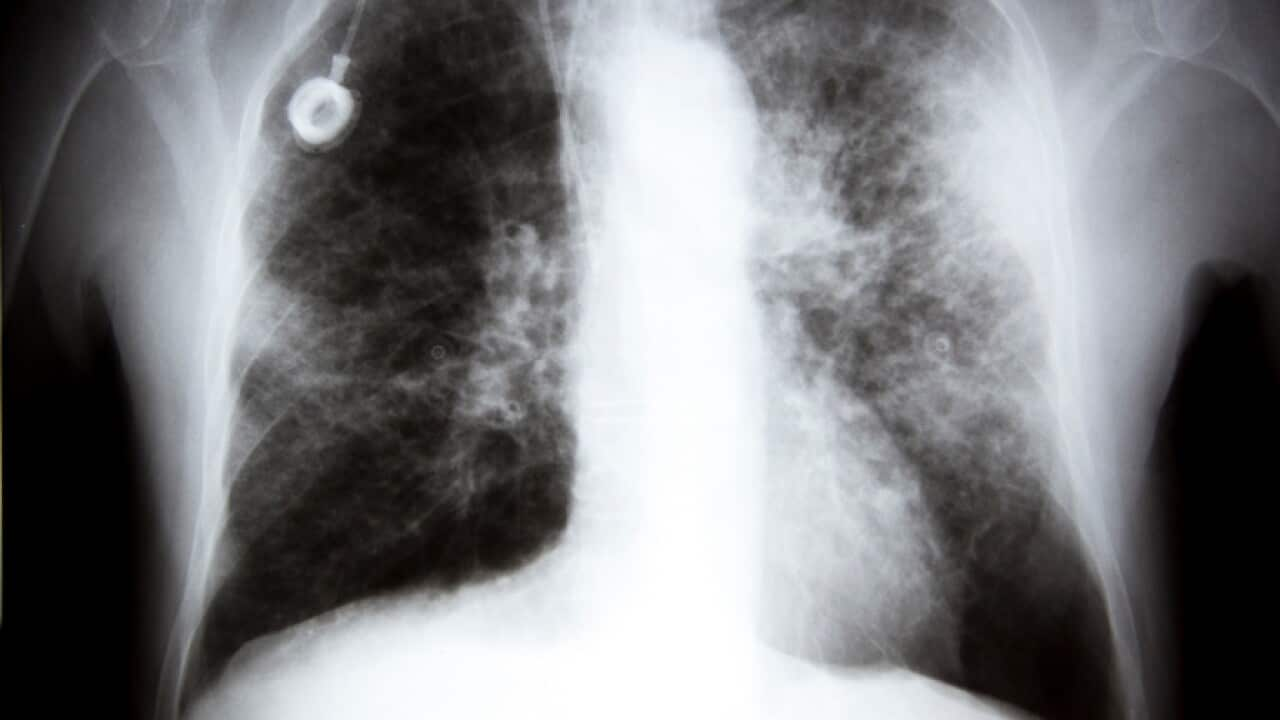

Screening for lung cancer has long been seen as too expensive and sometimes too unreliable. But with the disease now recognised as the deadliest type of cancer in Australia, experts are urging a lifesaving rethink on how to detect it early.